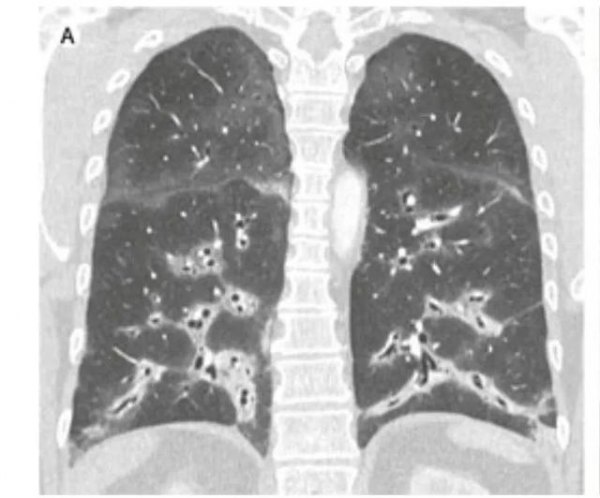

胸部高分辨率CT掃描(圖)顯示肺下葉病變明顯,支氣管血管周圍有雙側實變,機化性肺炎。